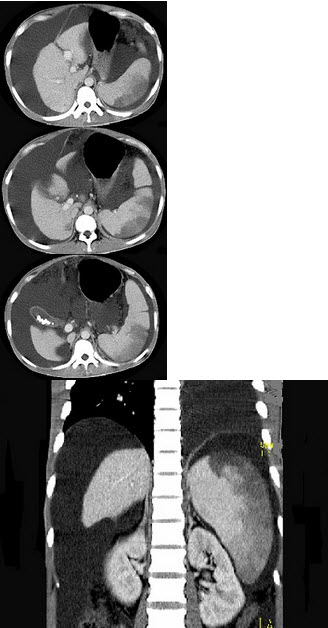

患者男,29岁,乙肝病史10余年,腹胀,有移动性浊音,影像检查如图,最全面的诊断是( )

A:肝硬化

B:肝硬化腹水

C:肝硬化腹水、脾梗、胆囊结石

D:大网膜膈下间位及脾梗

E:胆结石及脾梗